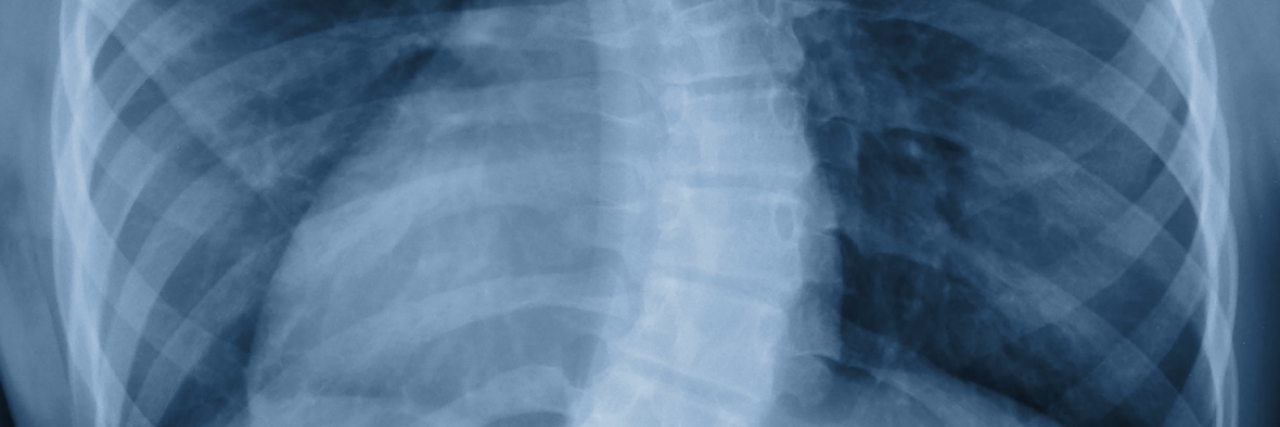

My own daughter was diagnosed with scoliosis when she was 14, and it was only then that I realized how traumatic the experience had been. Her scoliosis is a lesser degree than mine, so she doesn’t require bracing, but upon seeing her X-rays I nearly vomited.